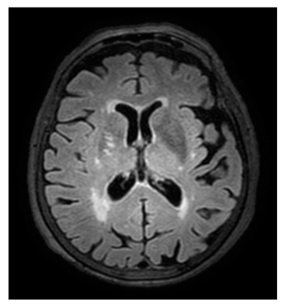

- White matter hyperintensities (WMH): Classified using the Fazekas scale (0–3) [21].

Regarding measurements of cerebrovascular disease, there were numerous statistically significant differences between MD and controls, namely the following: higher mean Fazekas score in MD (1.1 ± 0.8 in MD vs. 0.75 ± 0.8 in controls, p = 0.013); higher EPVStotal in MD (1.20 ± 0.9 in MD vs. 0.71 ± 0.8 in controls, p = 0.001);